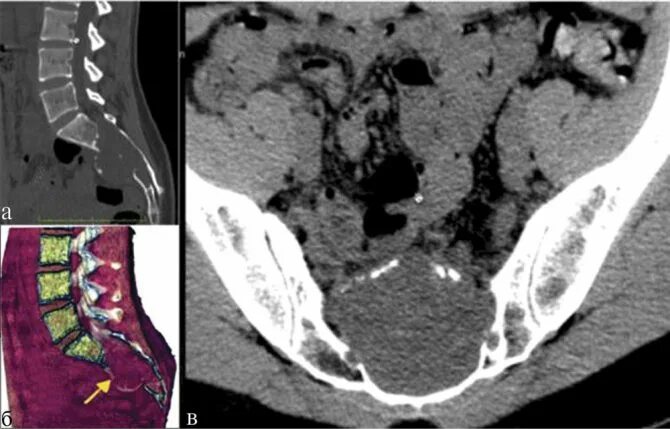

Метастазы в крестце